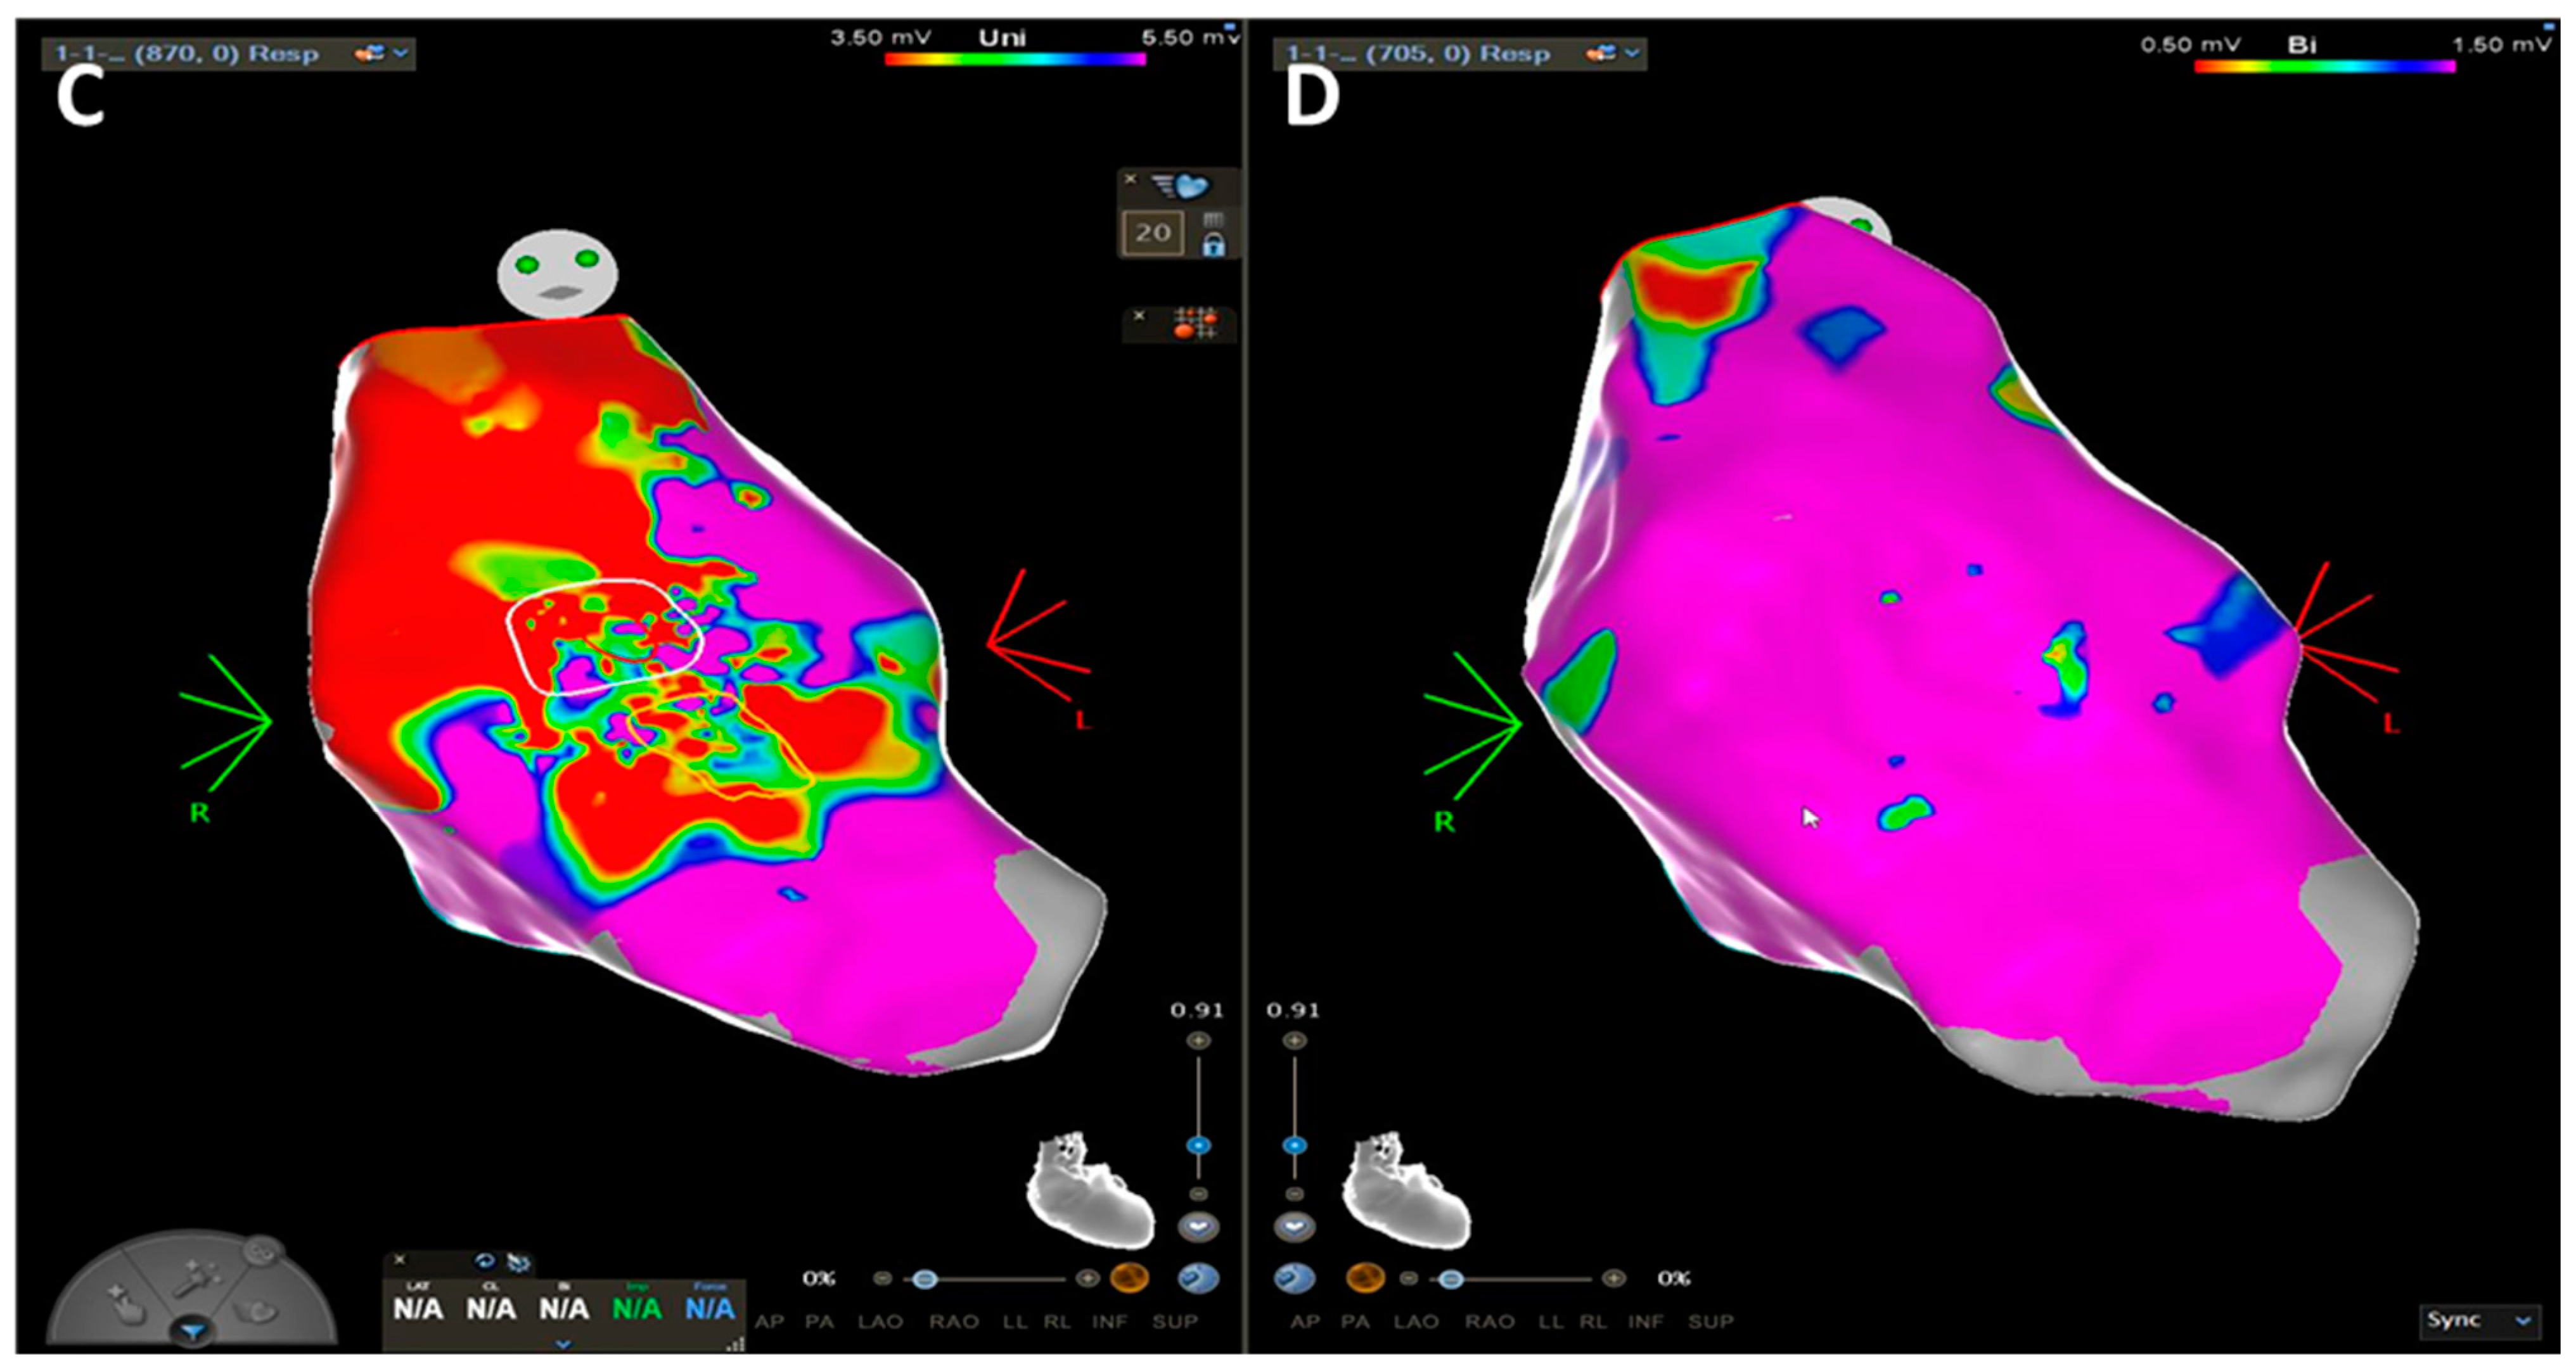

In sudden cardiac death risk evaluation, three-dimensional electroanatomic voltage mapping (EVM) offers the potential to identify the presence, location, and extent of the pathological substrate of ACM by detection of low-voltage areas that correspond to regions of RV myocardial loss and fibrofatty replacement [76]. Corrado et al. tested the hypothesis that RV electroanatomic low-amplitude areas were significantly associated with the histopathological finding of myocyte loss and fibrofatty replacement in endomyocardial biopsy [76]. This peculiar pathological process leads to islets of residual myocytes interspersed among adipocytes and fibrous tissue, providing an ideal milieu for re-entrant VT [77]. Similarly, case series suggested that low-voltage areas on invasive EVM could identify ACM at an earlier stage as compared to LGE and fatty infiltration on CE-CMR [78].

This “electroanatomic scar” area is defined as an area ≥ 1 cm2, including at least three adjacent points with bipolar signal amplitude < 0.5 mV. The color display for depicting normal and abnormal voltage myocardium ranges from “red” representing “electroanatomic scar tissue” (amplitude < 0.5 mV) to “purple” representing “electroanatomic normal tissue” (amplitude ≥ 1.5 mV). Intermediate colors represent the “electroanatomic border zone” (signal amplitudes between 0.5 and 1.5 mV) (1,3). A relatively sharp border, as identified by a steep spatial voltage gradient, could be used to demarcate the dysplastic regions. Unipolar voltage (UV) mapping of RV endocardium has been explored to predict the disease and the epicardial arrhythmogenic substrates. Evaluation of the epicardial abnormal substrates can be achieved using the RV endocardial unipolar voltage mapping with a cut-off value of 5.5 mV, and the abnormal area is correlated to the epicardial scar in ACM, although the different cut-off value of 4.4 mV has been proposed through the site-by-site comparison [79]. The previous studies based on CE-CMR imaging also supported that the bipolar low-voltage area and the territories displaying abnormal EGMs were correlated to the transmural scar [79,80]. In addition, even in the absence of an RV scar in CMR, parameters significantly associated with electroanatomic low-voltage areas are right precordial QRS prolongation, low-voltage QRS in the limb leads, and late potentials. Accordingly, intracardiac EGMs recorded from within the electroanatomic RV low-voltage areas often appeared fractionated with significantly prolonged duration and extended beyond the offset of the surface QRS compared with EGMs recorded from normal-voltage areas [78]. Hence, the ability to identify the dysplastic process by the presence of low-amplitude EGMs may be used as a new criterion in these patients’ work-up [75]. Considering the extensive pathological substrate due to the fact that the disease process in ACM initiates from the epicardium toward the endocardium, it is important to emphasize the relevance of a comprehensive and extensive substrate-based ablation strategy that incorporates endocardial (ENDO) and, if still inducible, epicardial (EPI) ablation to achieve the long-term VT control [77]. The 2022 ESC guidelines for the management of patients with ventricular arrhythmias and the prevention of sudden cardiac death recommended (class IIa, level of evidence C) ENDO and adjuvant EPI substrate ablation in patients with ACM and recurrent, symptomatic sustained monomorphic VT (SMVT), ICD shocks for SMVT despite anti-arrhythmogenic drugs or beta-blockers, or persistent inducibility after ENDO-only ablation.

Figure 5.

CE-CMR images in patients with ACM without RV morpho-functional abnormalities and LGE. (A) Short axis two-chamber view. (B) Long axis four-chamber view. (C) RV electroanatomic mapping depicting an epicardial scar on the RV free wall. Unipolar voltage map showing low voltages consistent with an epicardial scar. (D) Bipolar voltage map showing normal voltages.